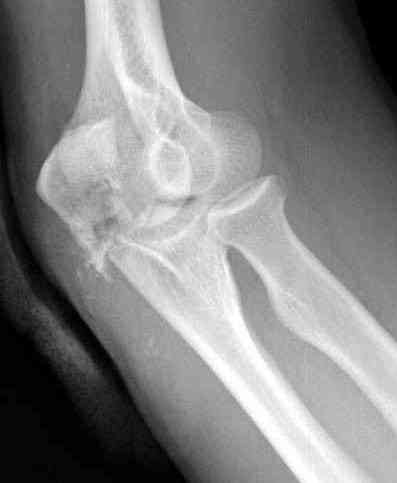

Здесь выставлены несколько случаев и варианты фиксации локтевого отростка, некоторые в комбинации с другими переломами.

3 вариант

перелом с capitelum humerus и проксимальной трети улна